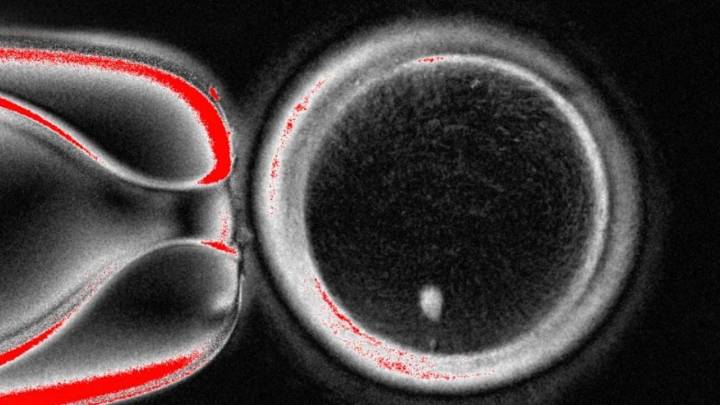

AP.- Un equipo científico logró, a partir de células de piel, generar óvulos humanos fértiles que fueron fecundados . Se considera que este desarrollo, que no fue tan exitoso como se esperaba, es un paso fundamental para, en un futuro no muy lejano, ayudar a las personas a concebir hijos con los que esté genéticamente relacionados.

Si bien el experimento fue exitoso en la generación de las células reproductoras femeninas, se detectaron anomalías en los cromosomas de los óvulos, por lo que el equipo de la Universidad de Salud y Ciencia de Oregon (OHSU por su sigla en inglés) advirtió que podría tomar u